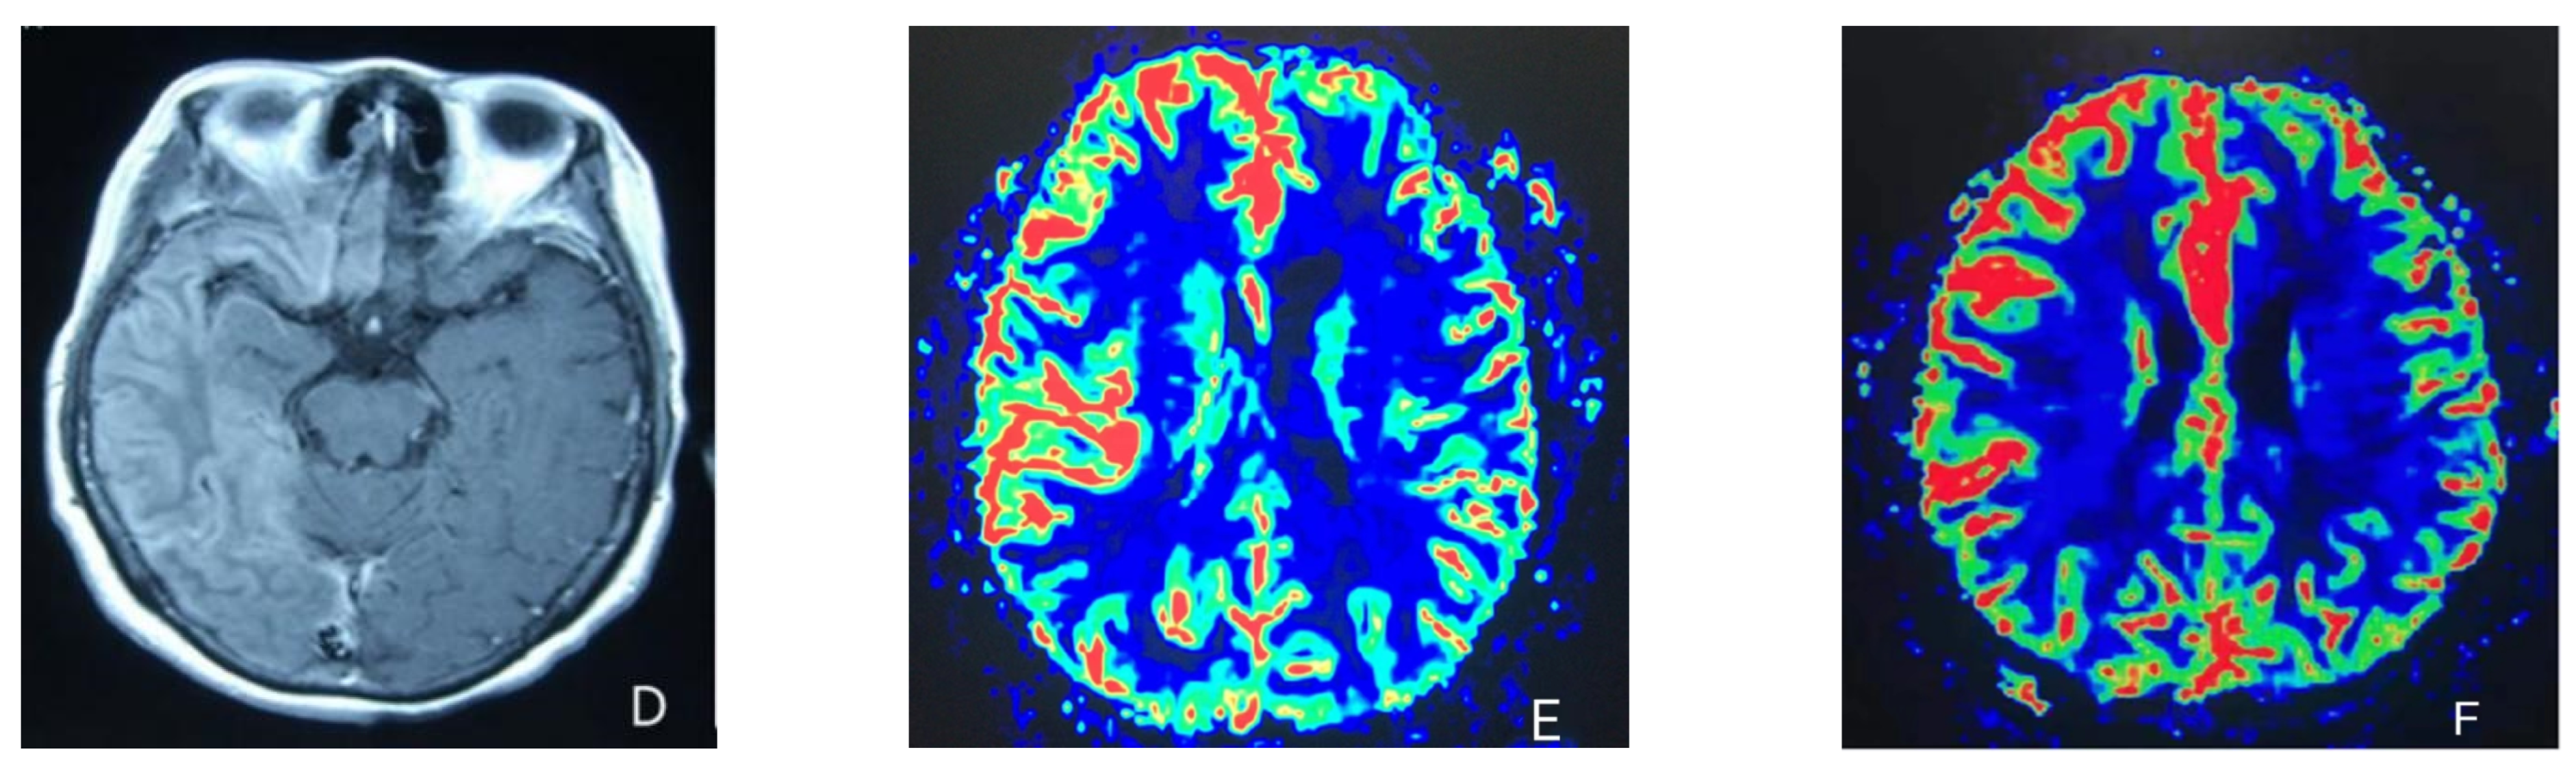

2. Case Presentation

- Iizuka, T.; Tominaga, N.; Kaneko, J.; Sato, M.; Akutsu, T.; Hamada, J.; Sakai, F.; Nishiyama, K. Biphasic neurovascular changes in prolonged migraine aura in familial hemiplegic migraine type 2. J. Neurol. Neurosurg. Psychiatry 2015, 86, 344–353. [Google Scholar] [CrossRef] [PubMed]